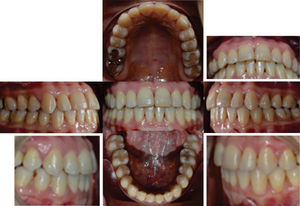

Facially, she presents a concave profile, mesofacial pattern, decreased upper facial third, asymmetry, neutral smile, lip competence and a slightly everted lower lip. Upon clinical examination and intraoral analysis, it was observed bilateral molar class III, a canine class III, a 3mm overbite, -2mm overjet, moderate lower dental crowding, dental midline deviation, ovoid upper and lower arch form, unilateral anterior and posterior crossbite and controlled generalized chronic periodontitis (Figures 3 at 5).

RESULTSThe arches were successfully correlated by eliminating the crossbite, the crowding was solved and the spaces were closed thus improving occlusal relationships and achieving molar and canine class I. The resulting overbite and overjet were adequate and remained under control. Periodontal status, aesthetics and function were favored (Figure 10) so the oral health and facial status of the patient was improved (Figure 11), emphasizing the harmony of a beautiful smile (Figure 12).